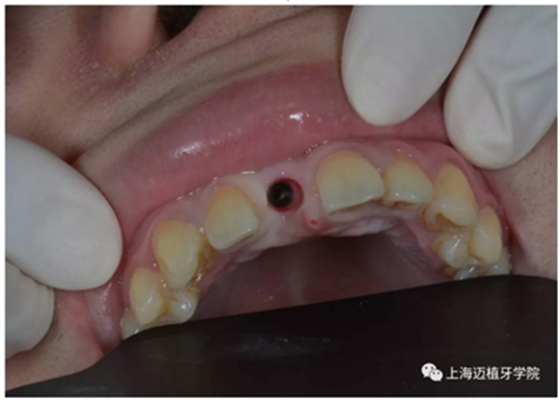

術(shù)后照

3月后恢復(fù)良好,上愈合基臺(tái)